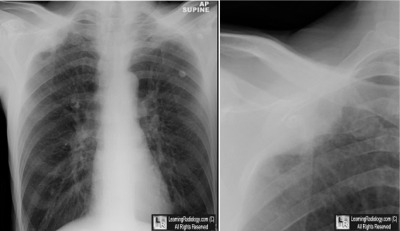

Frontal Chest Radiograph with Close-Up

- Apical Pleural Cap

- Pleural Lipoma